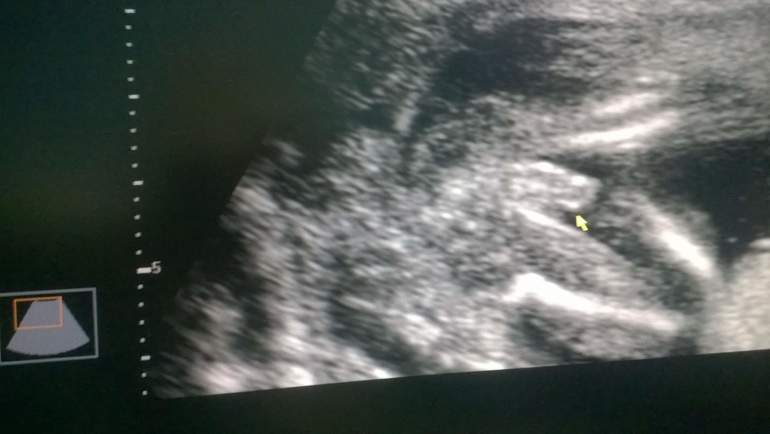

15-18 неделя )))

на радостях вызвала маму и поехали с ней в наш скринниг центр) ну фигушки я угада что попаду туда с первого раза... запись аж за 2 недели в перед!!! записали меня на 26 июня...нууу скоро уже!!! вышли от туда гляжу мамка растроенная... на внучка говорит посмотреть хотела, а нам там сказали что срок уже большой не плохо бы сделать контрольное УЗИ... Мамуля на радостях) прыгнули в ближайшее такси и помчались в любимую ЖК!!!))) фух!!! очередей не было и мы сразу зашли, улеглась... волнуюсь))) все таки в прошлый раз сказали что 80% мальчик а сон на днях показал мне девчушку... ну давай расматривать... ттт развитие идет хорошо уже не помещаемся в экран либо головушка с пузиком либо пузик с ножками))) малышок видимо спал на тот момент и спал ооочень удачно что мы расмотрели все!!!!!! ну всееее 100% мальчишка!!! мамулька давольная я тем более))) Профиль у малыша уже видно что мой!!! ))) мамуля попрасила кадр на память еще не просто малыша, а писю пожалуйста!!! не зря!!! дома захотели посматреть на этот кадр ВСЕ!!! прикреплю его к этой заметке тоже) на память) Муж мой рад безумно!!! уже открыто показывает радость и стал больше проявлять интерес к пузику))) целует, разговаривает, даже музыку ставит слушать правда настаивает исключительно на своей музыке чтобы вкус был папин))) эээх это надоже пузу давать слушать Король и Шут))) не я не против есть у них хорошие песни и сказки я ооочень люблю ноооо мне по вкусу больше спокойная ЧиллАут музыка) без папы дома мы слушаем именно ее)) а ещееее наконецто прошел токсикоз!!! но теперь я к сожалению исключительный веган... овощи фрукты зелень... сладкое, мясо буеееее!!! никогда бы не подумала что смогу без шоколада и мяса хоть денек провести))) схуднула видимо на такой диете... набрала за все недели беременности только 1 кг!!! при моем постоянном весе 58... теперь я 59... и то это только вес матки малыша и водички в нем! конечно было б хорошо набирать вес только пузом))) а еще в Ташкенте наступила чилля... жара блин невыносимая!!! на дню несколько раз ополаскиваюсь и пью воды ну оооооочень много!!! Хочу арбуззззз!!! холодный!!! но муж не разрешает ни у нас еще токсичные... эээээээээх... скорей бы июль! и я буду есть их тоннами!!!))))